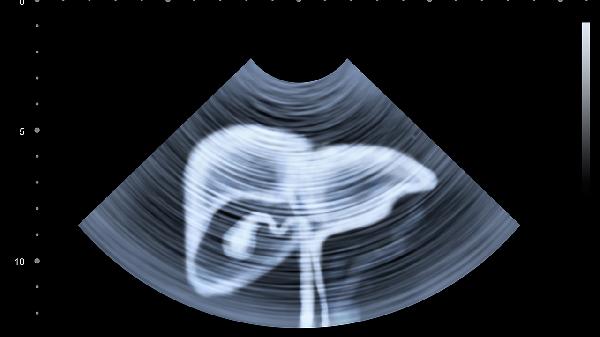

每周检测转氨酶、胆红素等肝功能指标,超声检查观察肝脏形态变化。生长发育曲线监测体重、头围增长情况。出现嗜睡、拒食、皮肤瘀斑等恶化症状需立即就医。